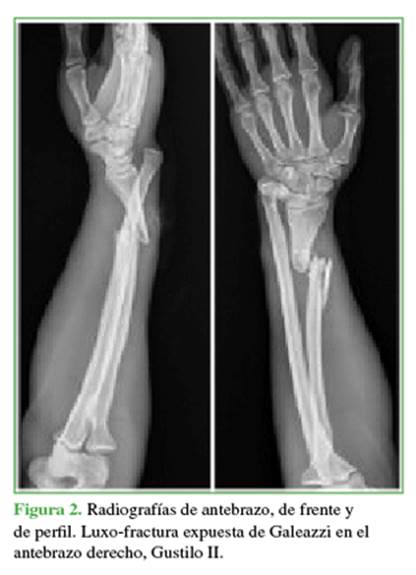

Hombre de 39 años de edad, que ingresó en el Servicio de Urgencias tras sufrir politraumatismos por un accidente de tránsito en motocicleta. Se diagnosticó una luxo-fractura expuesta de Galeazzi en el antebrazo derecho, Gustilo II (fractura diafisaria conminuta de radio y luxación radiocubital distal irreductible) (Figuras 1 y 2), por lo que se le indicaron antibióticos y cirugía de urgencia según el protocolo para fracturas expuestas. A los siete días, se procedió a la reducción abierta y fijación interna definitivas del radio derecho más la estabilización de la articulación radiocubital distal, con un buen resultado clínico-radiológico inicial (Figura 3).